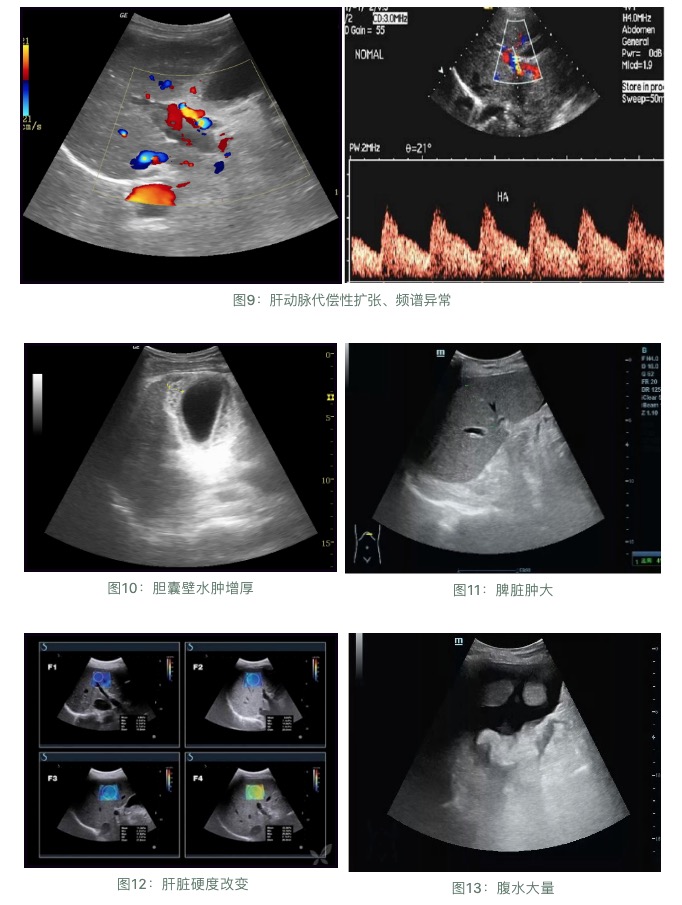

1.蜘蛛痣

一般情況下,肝硬化患在早期的時(shí)候,他們的面部、頸部、胸部或者是肩頭,會(huì)明顯的出現(xiàn)部分?jǐn)U張的皮膚小動(dòng)脈,并且這些皮膚小動(dòng)脈會(huì)呈現(xiàn)出樹枝狀的輻射,就像一只蜘蛛,這就是我們通常所說的蜘蛛痣。當(dāng)我們按住蜘蛛痣,他周圍的分支就會(huì)立馬消失。蜘蛛痣是肝臟疾病的最明顯的癥狀之一。

2.乏力、厭食、惡心

肝臟受損之后,有時(shí)候膽汁無法正常的分泌,加上身體的損傷,常常會(huì)有食欲不振的現(xiàn)象。尤其是肝臟病變,其實(shí)也消耗了很多的能量,所以說,出現(xiàn)乏力、失眠、多夢(mèng)的癥狀。

3.食欲減退

肝硬化出現(xiàn)后,肝臟受到的損傷日益明顯。肝臟作為消化系統(tǒng)的一部分,由于肝硬化導(dǎo)致門靜脈壓力增高,胃腸道出現(xiàn)淤血,胃腸道分泌與吸收出現(xiàn)功能紊亂;颊邥(huì)出現(xiàn)相應(yīng)的消化不良,食欲減退等,有時(shí)還有惡心嘔吐的表現(xiàn)。

4.面部變化

肝早期硬化會(huì)表現(xiàn)在患者的面容上面,肝病患者的面容一般都是晦暗,黝黑,失去光澤的。因?yàn)樾⊙艿臄U(kuò)張嚴(yán)重,部分患者會(huì)出現(xiàn)局部發(fā)紅癥狀。因?yàn)楸旧砘颊哓氀,?huì)顯示臉色不佳,臉色蒼白。

5.腹痛

腹痛,可因脾腫大、脾周圍炎、肝細(xì)胞壞死、肝周圍炎、門靜脈炎等而致腹痛,但大多不明顯,或是“絲絲拉拉”地痛。